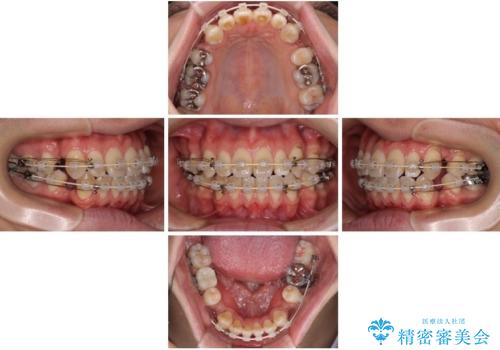

装置は、透明感のあるクリアブラケットとホワイトコーティングされたワイヤーを使用した、目立ちにくい審美装置を選択。

周囲に気づかれにくく、日常生活にも自然に溶け込みます。

治療期間は約2年。

少しずつ前歯を後ろに下げていくことで、横顔のラインが整い、口元の“出っ張り感”が解消。